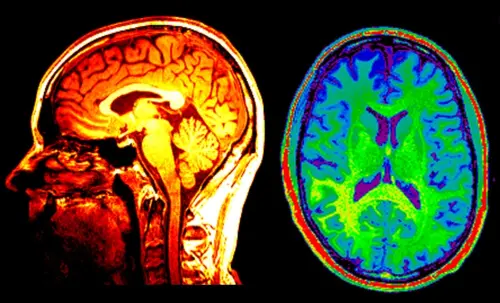

I ricercatori del Dartmouth College hanno valutato le amicizie e i legami sociali all'interno di un gruppo di circa 280 studenti laureati. Le scansioni cerebrali hanno rivelato che gli amici avevano le risposte del cervello più simili ai video. E gli amici degli amici avevano attività cerebrali più simili di amici di amici di amici.

Gli investigatori hanno scoperto che simili risposte MRI funzionali potevano essere utilizzate per prevedere non solo se una coppia era amica, ma anche la distanza sociale tra di loro.